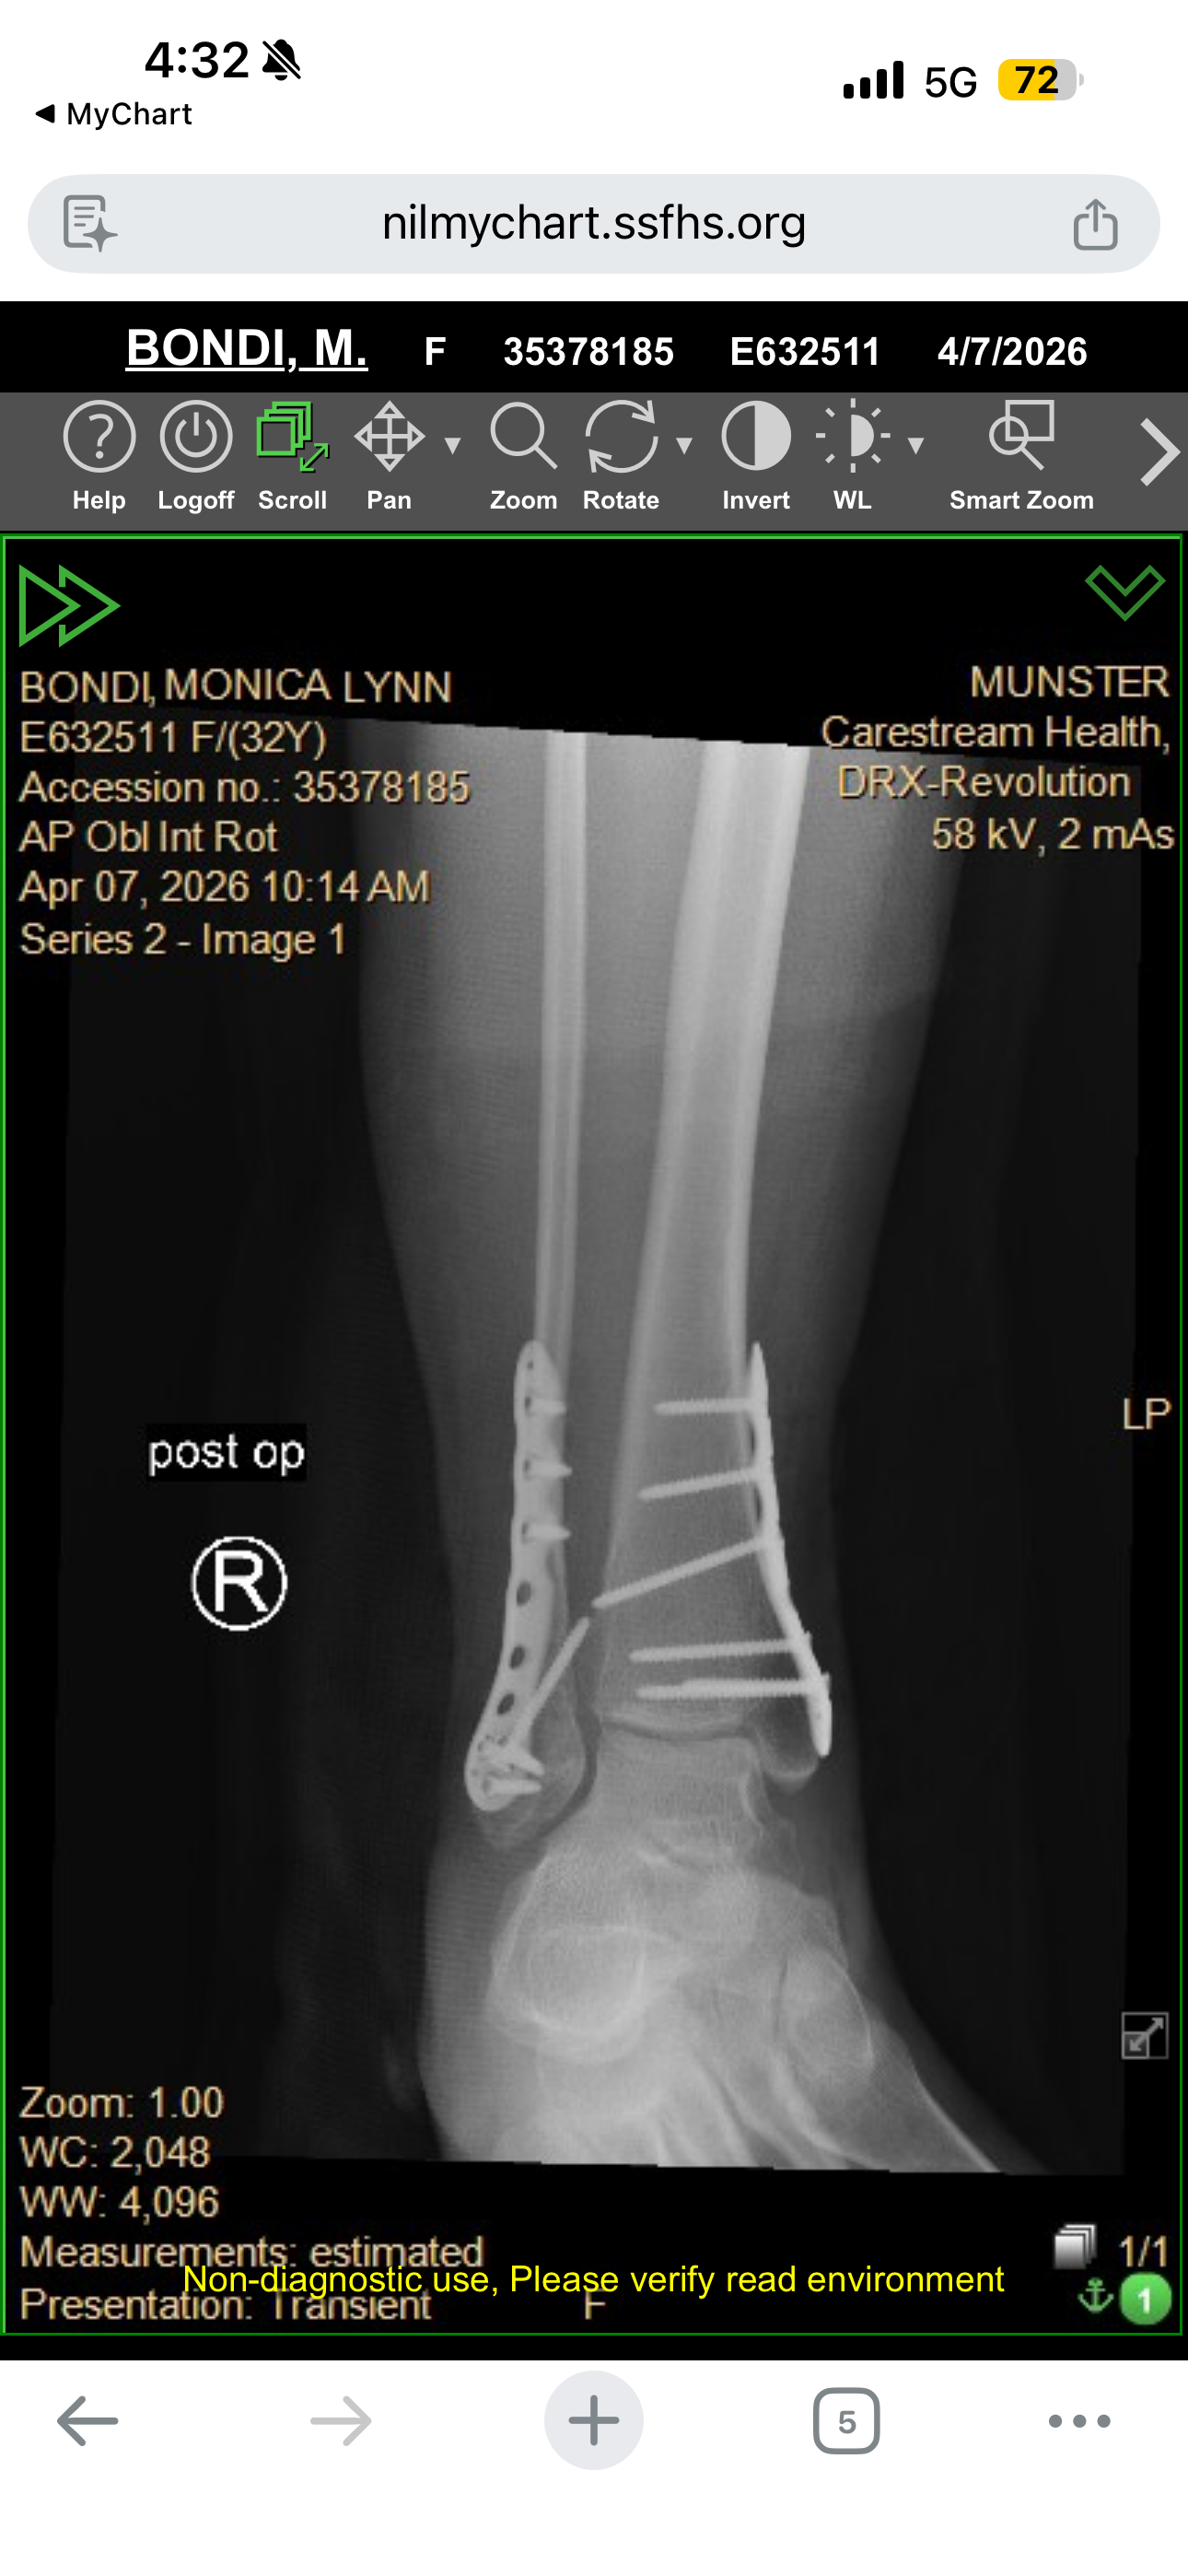

My name is Monica, and I'm a single mom of three wonderful kids. Recently, I experienced a life-changing accident when I jumped off my horse and broke every bone in my ankle. The injury was so severe that I needed surgery, which resulted in 13 screws and 2 plates being put into my ankle. The recovery process is long and challenging, and it's turned my world upside down.